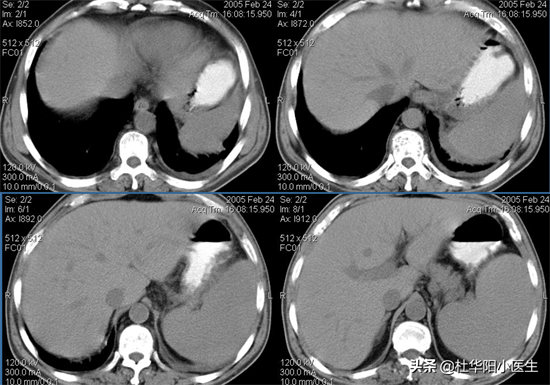

脾脏大小 脾脏正常解剖(CT)

脾脏正常解剖

脾脏外缘圆隆光滑,内缘呈分叶状,不同层面形态不同。大小变异较大,长12cm, 宽7cm,厚3~4cm。

•CT表现:CT判断有无脾增大,粗略的方法是用脾周肋单元估计,正常脾脏为5个肋单元以下,即2个肋间隙和3个肋骨或3个肋间隙和2个肋骨,大于5个肋单元则认为有脾增大,但扫描平面与脾脏长轴不平行,肋单元小于5个而下缘超过肝脏下缘也认为是有增大。密度均匀。

影像解剖

(1)位于左上腹部,上缘与在膈面相邻,下缘与左肾上腺、左肾上极邻,前缘与结肠脾曲邻。由腹膜包绕,是腹膜腔内器官。脾静脉在脾门处形成,在左肾、左膈脚、腹主动脉前方及胰腺后方走行与SMV汇合入门静脉。

(2)正常脾脏可有分叶或切迹,可突入到胰尾和左肾之间,下缘也可有切迹,CT可显示脾的小裂口。

(3)脾脏大小个体差异大,一般成人平均长为12cm。CT上显示脾脏形态因层面而异,上部和下部为新月形,脾门处呈内缘凹陷的半圆形或椭圆形。不超过5个肋单元,脾脏下缘超过肝脏下缘或其前、后缘超过中线均是脾脏增大的征象;

(4) 密度均匀一致,稍低于肝脏密度约8-10HU,+C扫描早期由于血流关系皮质强化明显髓质而呈密度不均表现即花斑脾,稍后皮髓质趋向一致;